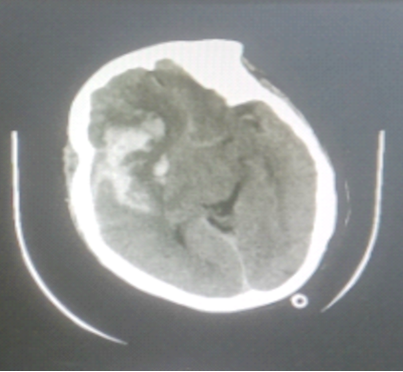

▲CT提示右侧额颞叶急性脑出血

患者病情危重,诊断考虑:右侧大脑中动脉瘤破裂并脑内血肿,占位效应明显,且有继续出血脑疝形成可能。我科手术团队经充分讨论后认为需急诊开颅脑动脉瘤夹闭术,患者家属同意后予急诊绿色通道送手术室手术治疗。术程顺利,术后患者苏醒,在院康复治疗中。